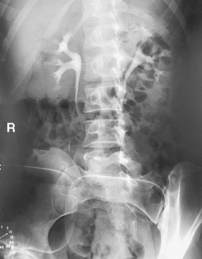

The air-barium distribution within the stomach and large intestine changes with various body positions. By knowing these distribution patterns, one can determine in which body position a radiograph was taken. Air always rises to the highest levels, and the heavy barium settles to the lowest levels (air is black, barium is white).

The fundus is located more posteriorly; therefore in the supine position it would be the lowest portion of the stomach and would be filled with barium.

In both prone and erect positions, the fundus would be filled with air as seen on the drawings below, with a straight air-barium line on the erect.

The ascending and descending portions are located more posteriorly, and thus more of these parts in general would be filled with barium (white) in the supine position and with air (black) in the prone position.

This much separation of barium and air occurs generally only with double-contrast barium-air studies.

Air-fluid levels would be seen in the erect position in which the air would rise to the highest position in each of the various sections of the large intestine, as shown in the accompanying figure.

Right and left decubitus projections (not shown on these drawings) also would demonstrate air-fluid levels, with air again rising to the highest portions.